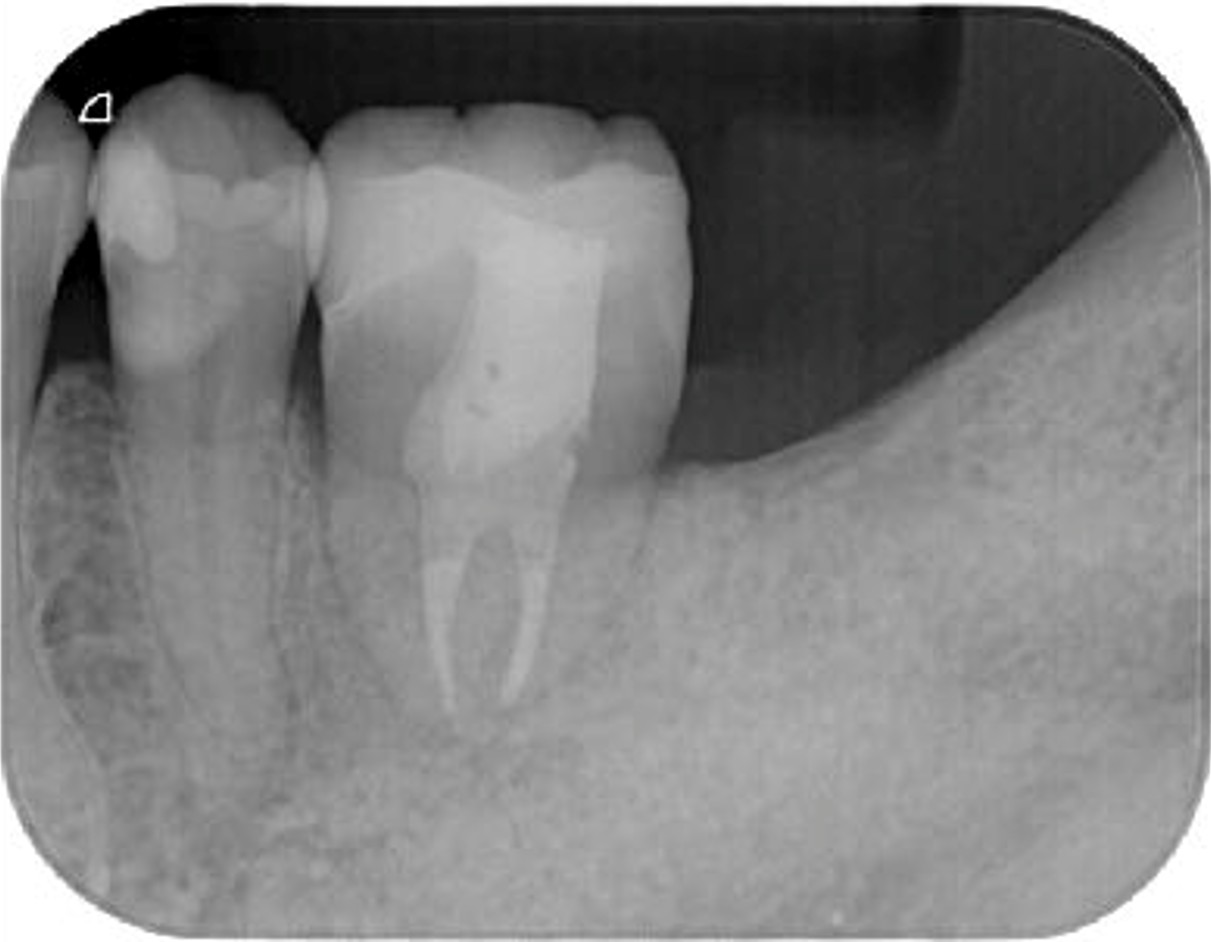

| 患者様データ | 40代 男性 |

| 来院時の主訴 | 「左下が痛くて噛めない。」 |

| 医院の診断 | 左下第一大臼歯歯根破折、慢性根尖性歯周炎 |